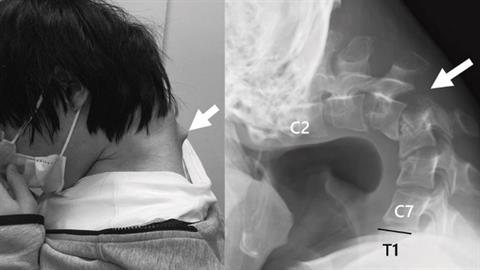

Το πιγούνι του ακουμπούσε μόνιμα στο στήθος του και χρειάστηκε χειρουργείο για να ξανασηκώσει το κεφάλι του